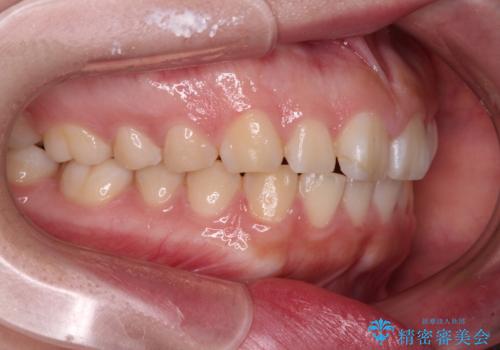

- 出っ歯と口の閉じにくさ、デコボコを気にして来院された患者様です。

口元の突出感を改善するため、上下左右第一小臼歯4本の抜歯を行い、ワイヤー装置による矯正治療を行うこととしました。